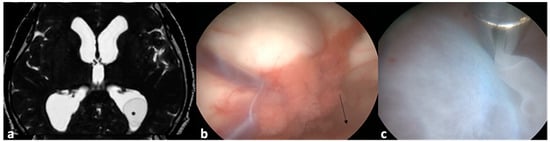

- Husain, M.; Jha, D.K.; Rastogi, M.; Husain, N.; Gupta, R.K. Neuro-endoscopic Management of Intraventricular Neurocysticercosis (NCC). Acta Neurochir. 2007, 149, 341–346. [Google Scholar] [CrossRef]

- Torres-Corzo, J.G.; Tapia-Pérez, J.H.; Vecchia, R.R.; Chalita-Williams, J.C.; Sánchez-Aguilar, M.; Sánchez-Rodríguez, J.J. Endoscopic Management of Hydrocephalus Due to Neurocysticercosis. Clin. Neurol. Neurosurg. 2010, 112, 11–16. [Google Scholar] [CrossRef] [PubMed]

- Proaño, J.V.; Torres-Corzo, J.; Rodríguez-Della Vecchia, R.; Guizar-Sahagun, G.; Rangel-Castilla, L. Intraventricular and Subarachnoid Basal Cisterns Neurocysticercosis: A Comparative Study Between Traditional Treatment Versus Neuroendoscopic Surgery. Child’s Nerv. Syst. 2009, 25, 1467–1475. [Google Scholar] [CrossRef] [PubMed]

- Goel, R.K.; Ahmad, F.U.; Vellimana, A.K.; Suri, A.; Chandra, P.S.; Kumar, R.; Sharma, B.S.; Mahapatra, A.K. Endoscopic Management of Intraventricular Neurocysticercosis. J. Clin. Neurosci. 2008, 15, 1096–1101. [Google Scholar] [CrossRef] [PubMed]

- Zhenye, L.; Chuzhong, L.; Xuyi, Z.; Songbai, G.; Peng, Z.; Jiwei, B.; Lei, C.; Xinsheng, W. Ventriculoscopic Approach for Intraventricular Neurocysticercosis: A Single Neurosurgical Center’s Experience. World Neurosurg. 2017, 107, 853–859. [Google Scholar] [CrossRef]

- Kaif, M.; Husain, M.; Ojha, B.K. Endoscopic Management of Intraventricular Neurocysticercosis. Turk. Neurosurg. 2019, 29, 59–65. [Google Scholar]

- Singh, S.; Marutirao, R.; Deora, H.; Das, K.K.; Bhaisora, K.S.; Sardhara, J.; Parab, A.; Mehrotra, A.; Srivastava, A.K.; Jaiswal, S.; et al. Endoscopic Route for Excision of Intraventricular Neurocysticercosis: Light At the End of the Tunnel. World Neurosurg. 2019, 125, e74–e81. [Google Scholar] [CrossRef] [PubMed]